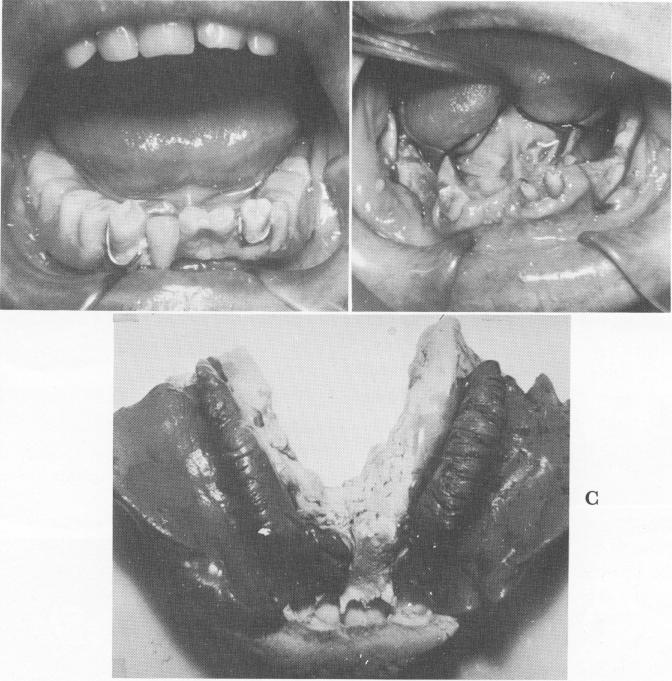

Fig. 12-57. A, A preoperative patient with only three anterior teeth remaining. B, The three teeth had been previously prepared for full crown coverage. The fibromucosal tissues are retracted posteriorly and bilaterally to expose the underlying bone. C, Bilateral rubber base (Neoplex) impressions are taken and picked up, if desired, with either a full arch plaster or an alginate impression, which includes the anterior tooth preparation.